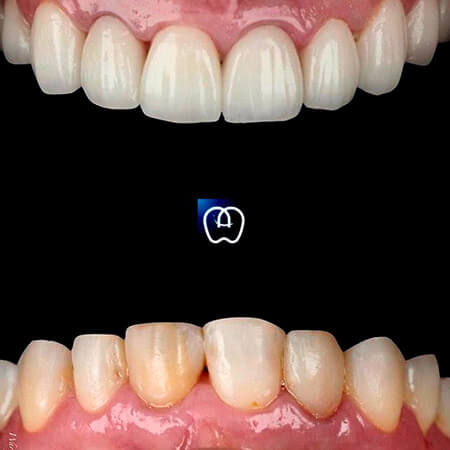

Galería de antes y después

Las especialidades de Álvarez & Arráez Odontología son: Odontólogo, Implantes dentales, Odontología láser, Odontología estética, Rehabilitación oral, Periodoncia, Endodoncia, Odontopediatra, Ortodoncia.